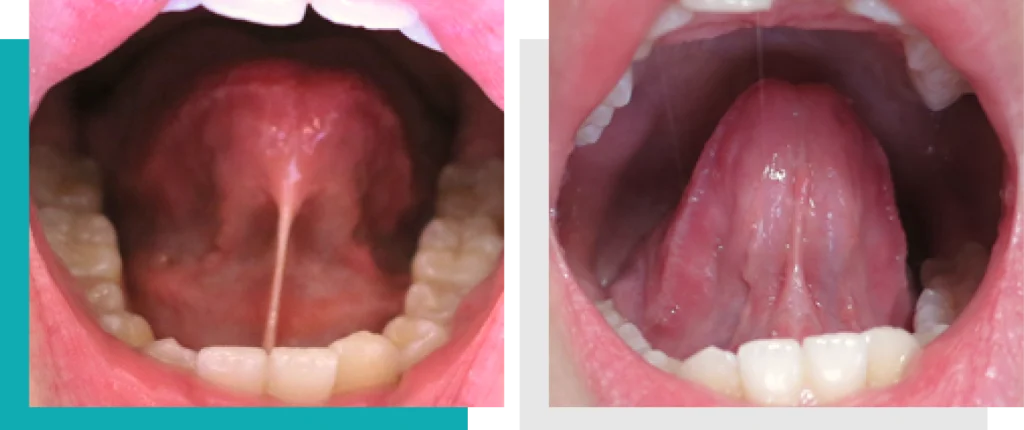

Frenectomías

Es la cirugía de los frenillos de la cavidad bucal, puede ser en los labios, lengua o encía lateral. Debe ser realizada por un cirujano en un pabellón de cirugía menor.